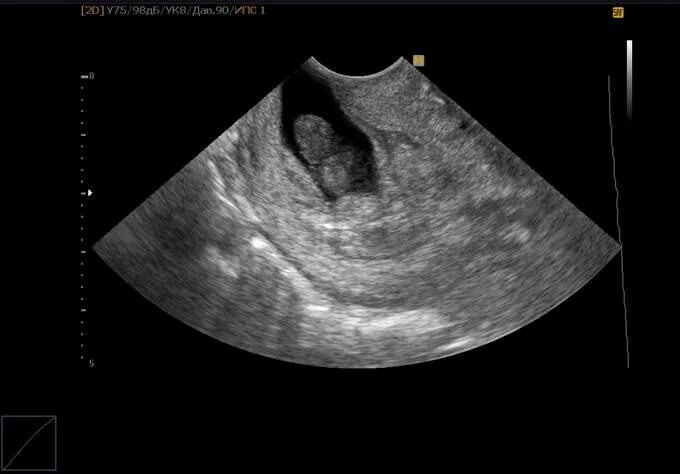

Как называется узи на ранних сроках